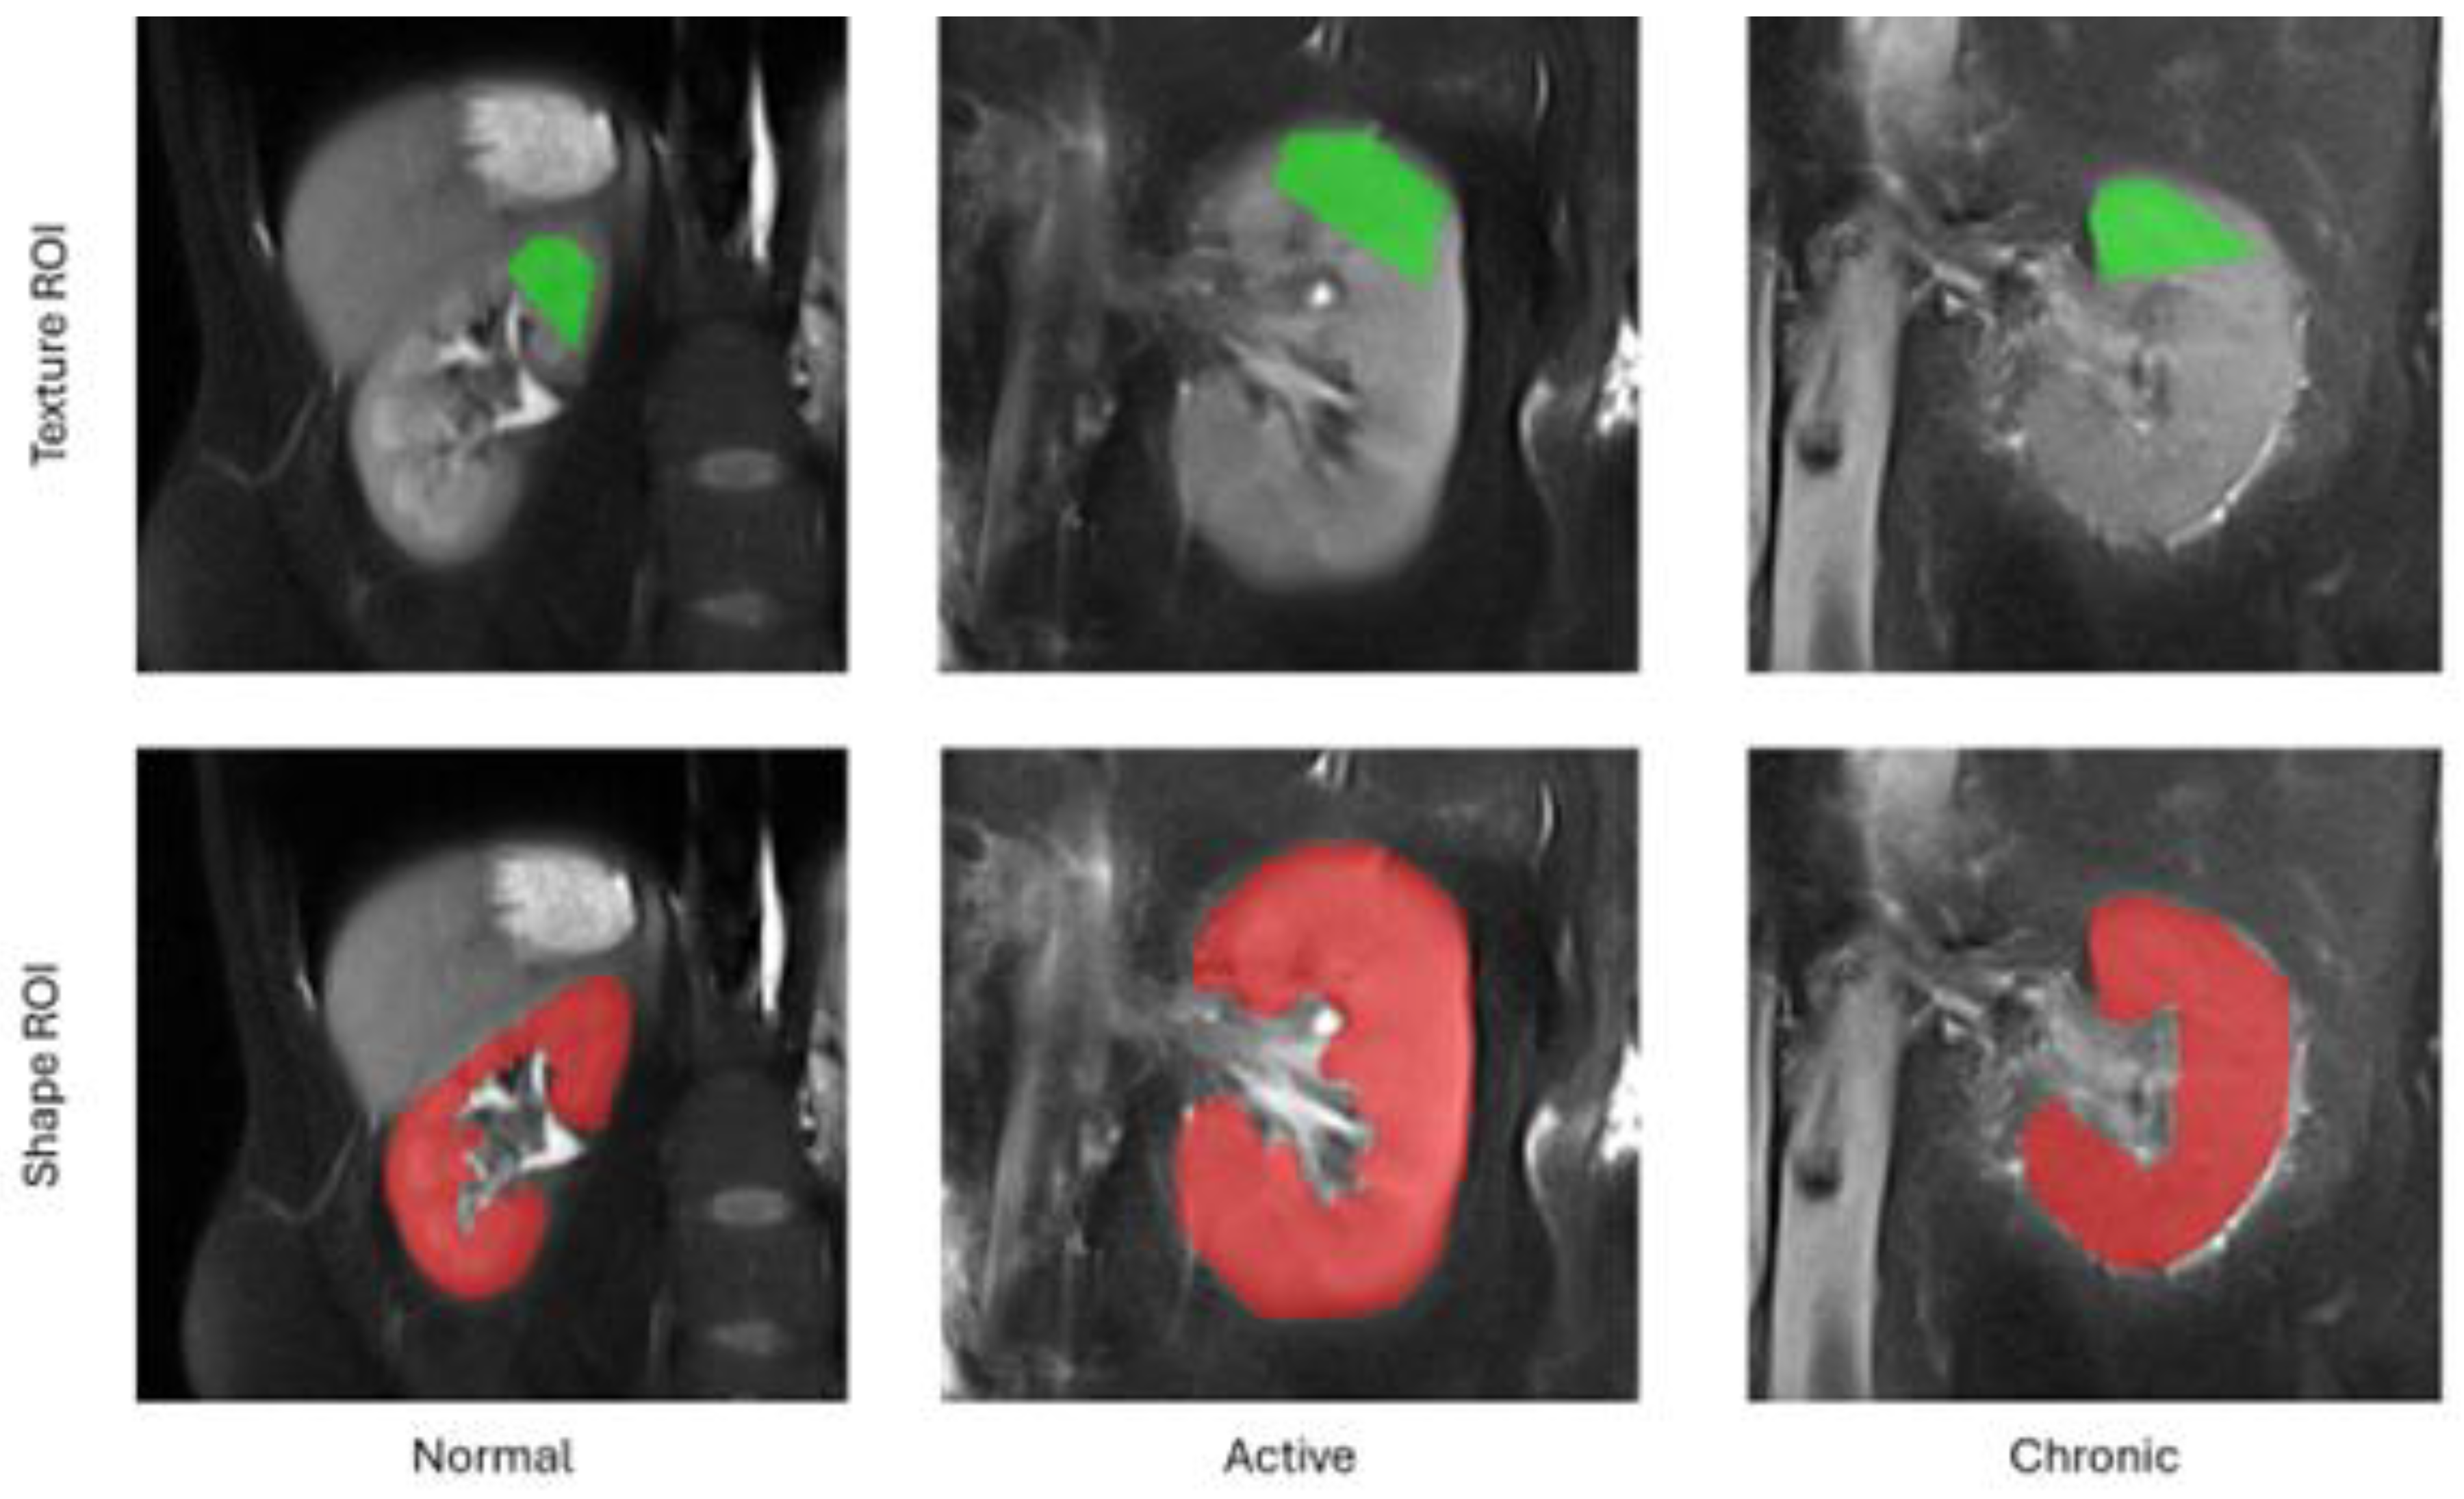

The feature extraction workflow in our study embraced the following steps. For each subject included in the study, we first selected from the entire 3D volume a middle cross-section of the kidney along the anterior-posterior acquisition axis. Then, a pentagonal region of interest (ROI) was manually drawn over the tissue area directly above the kidney pelvis (cf. Figure 1). The choice of this region for analysis was subject to the fact that it is anatomically most representative and most repetitively represented on MRI images. Also the pentagonal ROI was chosen since it occurred the simplest, yet sufficiently flexible shape adjustable to kidney geometry of an individual subject. Next, pixel intensities within the ROI were normalized to the range defined by this ROI mean intensity and the interval of +/- 3 standard deviations (so-called 3-sigma normalization). The normalization ensures that the computed features are independent from possibly various acquisition settings, scanner parameters drift during equipment lifetime or different measured signal energies resulting from patient-dependent magnetic field perturbations, i.e. all factors which affect final image brightness and contrast. Eventually, the texture analysis was performed within each patient ROI, and the computed feature vectors completed with a category label (1 – normal, 2 – active, 3 – chronic) were stored in an output CSV file.

In addition to texture analysis, we also determined a series of geometrical attributes. These were calculated for a whole 2D shape of the kidney visible in the selected cross-section, i.e. the same slice of the 3D volume as chosen for TA. The set of morphological parameters consisted of 97 features which described kidney shape’s characteristics such as e.g. area, circularity, convexity, principal orientation, contour-skeleton attributes, second order moments of inertia, or perimeter profile attributes. Inclusion of this group of descriptors in the further analysis was motivated by the observation that texture alone does not encapsulate all the differences in tissue appearance wrt. lesion category, and it is the kidney shape which improves performance of the ultimate classification model. As a final remark, please note that each kidney image was represented in the final data set by only one feature vector. Hence, there’s no risk of data leakage while partitioning the vectors into train and test folds during the exploratory analysis.

Figure 1. Example regions of interest for texture and shape analysis.